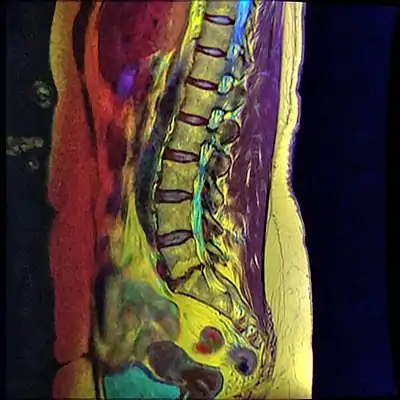

Retrolisthesis of L5-S1